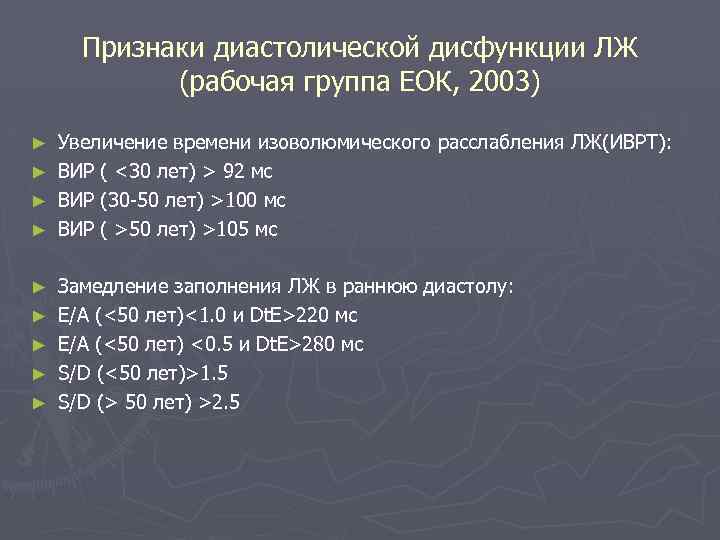

Признаки диастолической дисфункции ЛЖ (рабочая группа ЕОК, 2003) ► ► ► ► ► Увеличение времени изоволюмического расслабления ЛЖ(ИВРТ): ВИР ( <30 лет) > 92 мс ВИР (30 -50 лет) >100 мс ВИР ( >50 лет) >105 мс Замедление заполнения ЛЖ в раннюю диастолу: Е/А (<50 лет)<1. 0 и Dt. E>220 мс Е/А (<50 лет) <0. 5 и Dt. E>280 мс S/D (<50 лет)>1. 5 S/D (> 50 лет) >2. 5